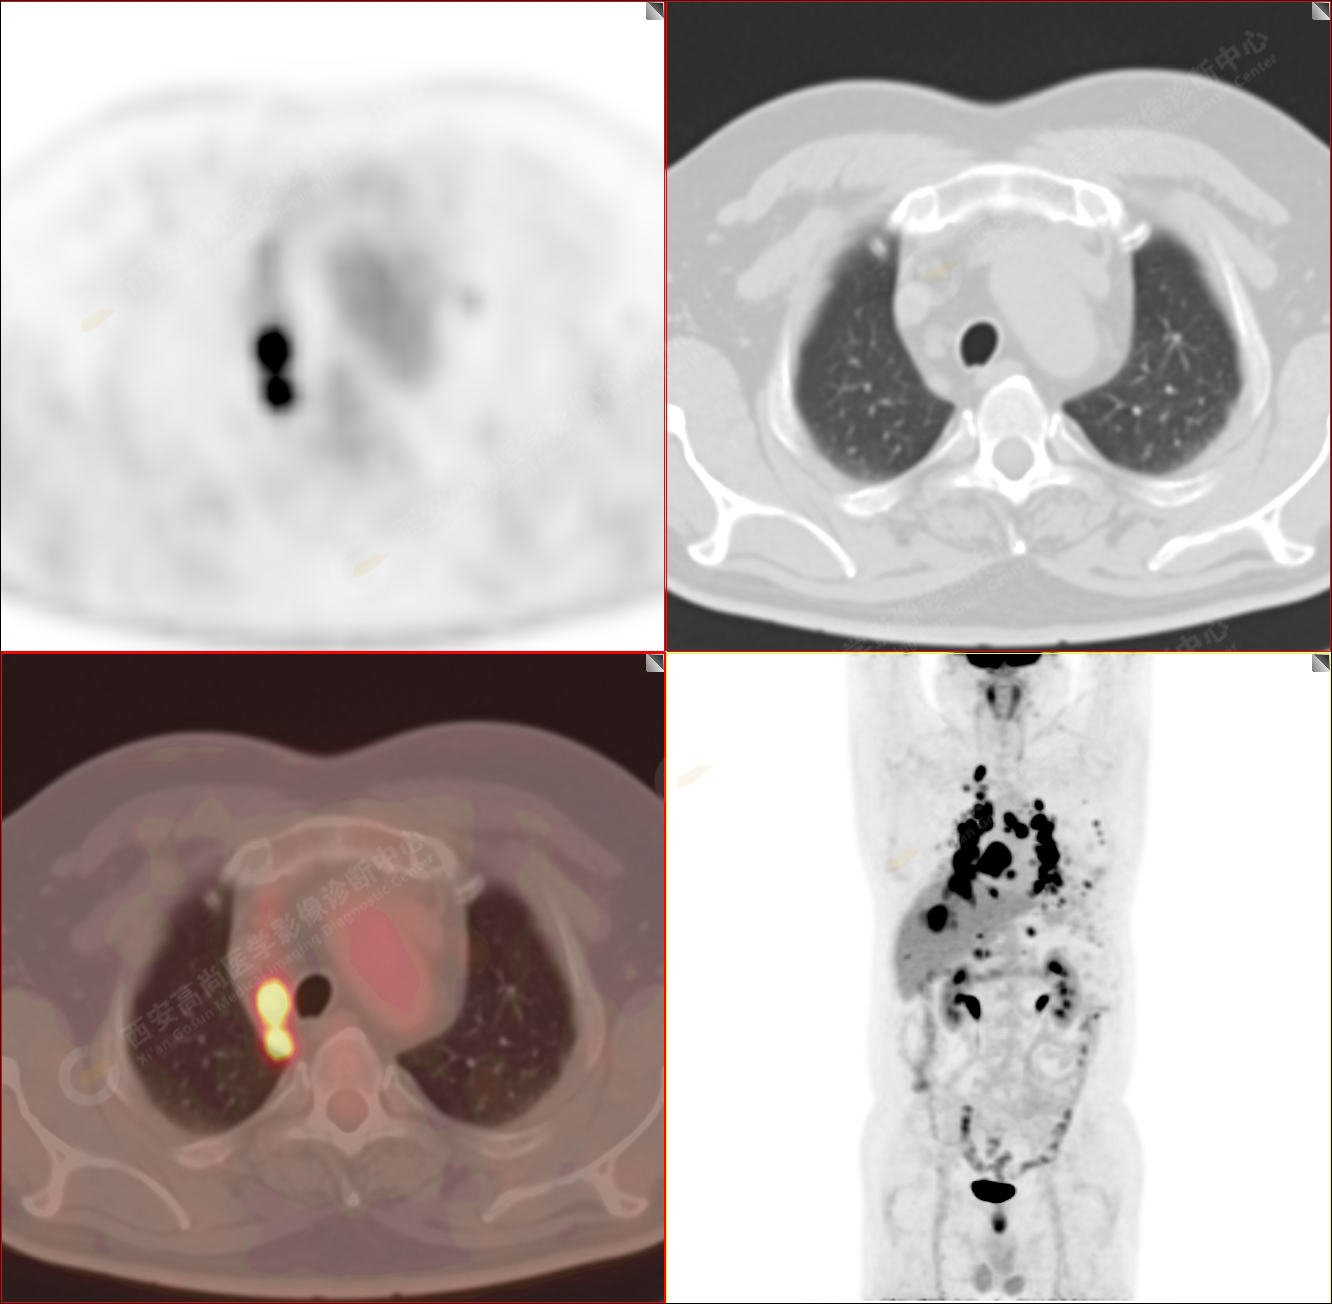

PET/CT-MR診斷結(jié)節(jié)病雙肺及全身多發(fā)淋巴結(jié)廣泛累及1例【西安高尚病例】

男性,53歲,頭暈半月入院,CT發(fā)現(xiàn)肺內(nèi)腫塊,雙肺多發(fā)大小不等實(shí)性及粟粒樣結(jié)節(jié),雙肺門(mén)及縱隔多發(fā)腫大淋巴結(jié)。病程中無(wú)發(fā)熱、胸悶氣及胸部不適。既往:左側(cè)肋骨外傷史。

PET-MR圖像